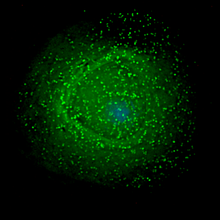

HIV infects vital cells in the human immune system such as helper T cells (specifically CD4+ T cells), macrophages, and dendritic cells. HIV infection leads to low levels of CD4+ T cells through a number of mechanisms including: apoptosis of uninfected bystander cells, direct viral killing of infected cells, and killing of infected CD4+ T cells by CD8 cytotoxic lymphocytes that recognize infected cells. When CD4+ T cell numbers decline below a critical level, cell-mediated immunity is lost, and the body becomes progressively more susceptible to opportunistic infections.

The term viral tropism refers to which cell types HIV infects. HIV can infect a variety of immune cells such as CD4+ T cells, macrophages, and microglial cells. HIV-1 entry to macrophages and CD4+ T cells is mediated through interaction of the virion envelope glycoproteins (gp120) with the CD4 molecule on the target cells and also with chemokine coreceptors.

Macrophage (M-tropic) strains of HIV-1, or non- syncitia-inducing strains (NSI) use the β-chemokine receptor CCR5 for entry and are, thus, able to replicate in macrophages and CD4+ T cells. This CCR5 coreceptor is used by almost all primary HIV-1 isolates regardless of viral genetic subtype. Indeed, macrophages play a key role in several critical aspects of HIV infection. They appear to be the first cells infected by HIV and perhaps the source of HIV production when CD4+ cells become depleted in the patient. Macrophages and microglial cells are the cells infected by HIV in the central nervous system. In tonsils and adenoids of HIV-infected patients, macrophages fuse into multinucleated giant cells that produce huge amounts of virus.